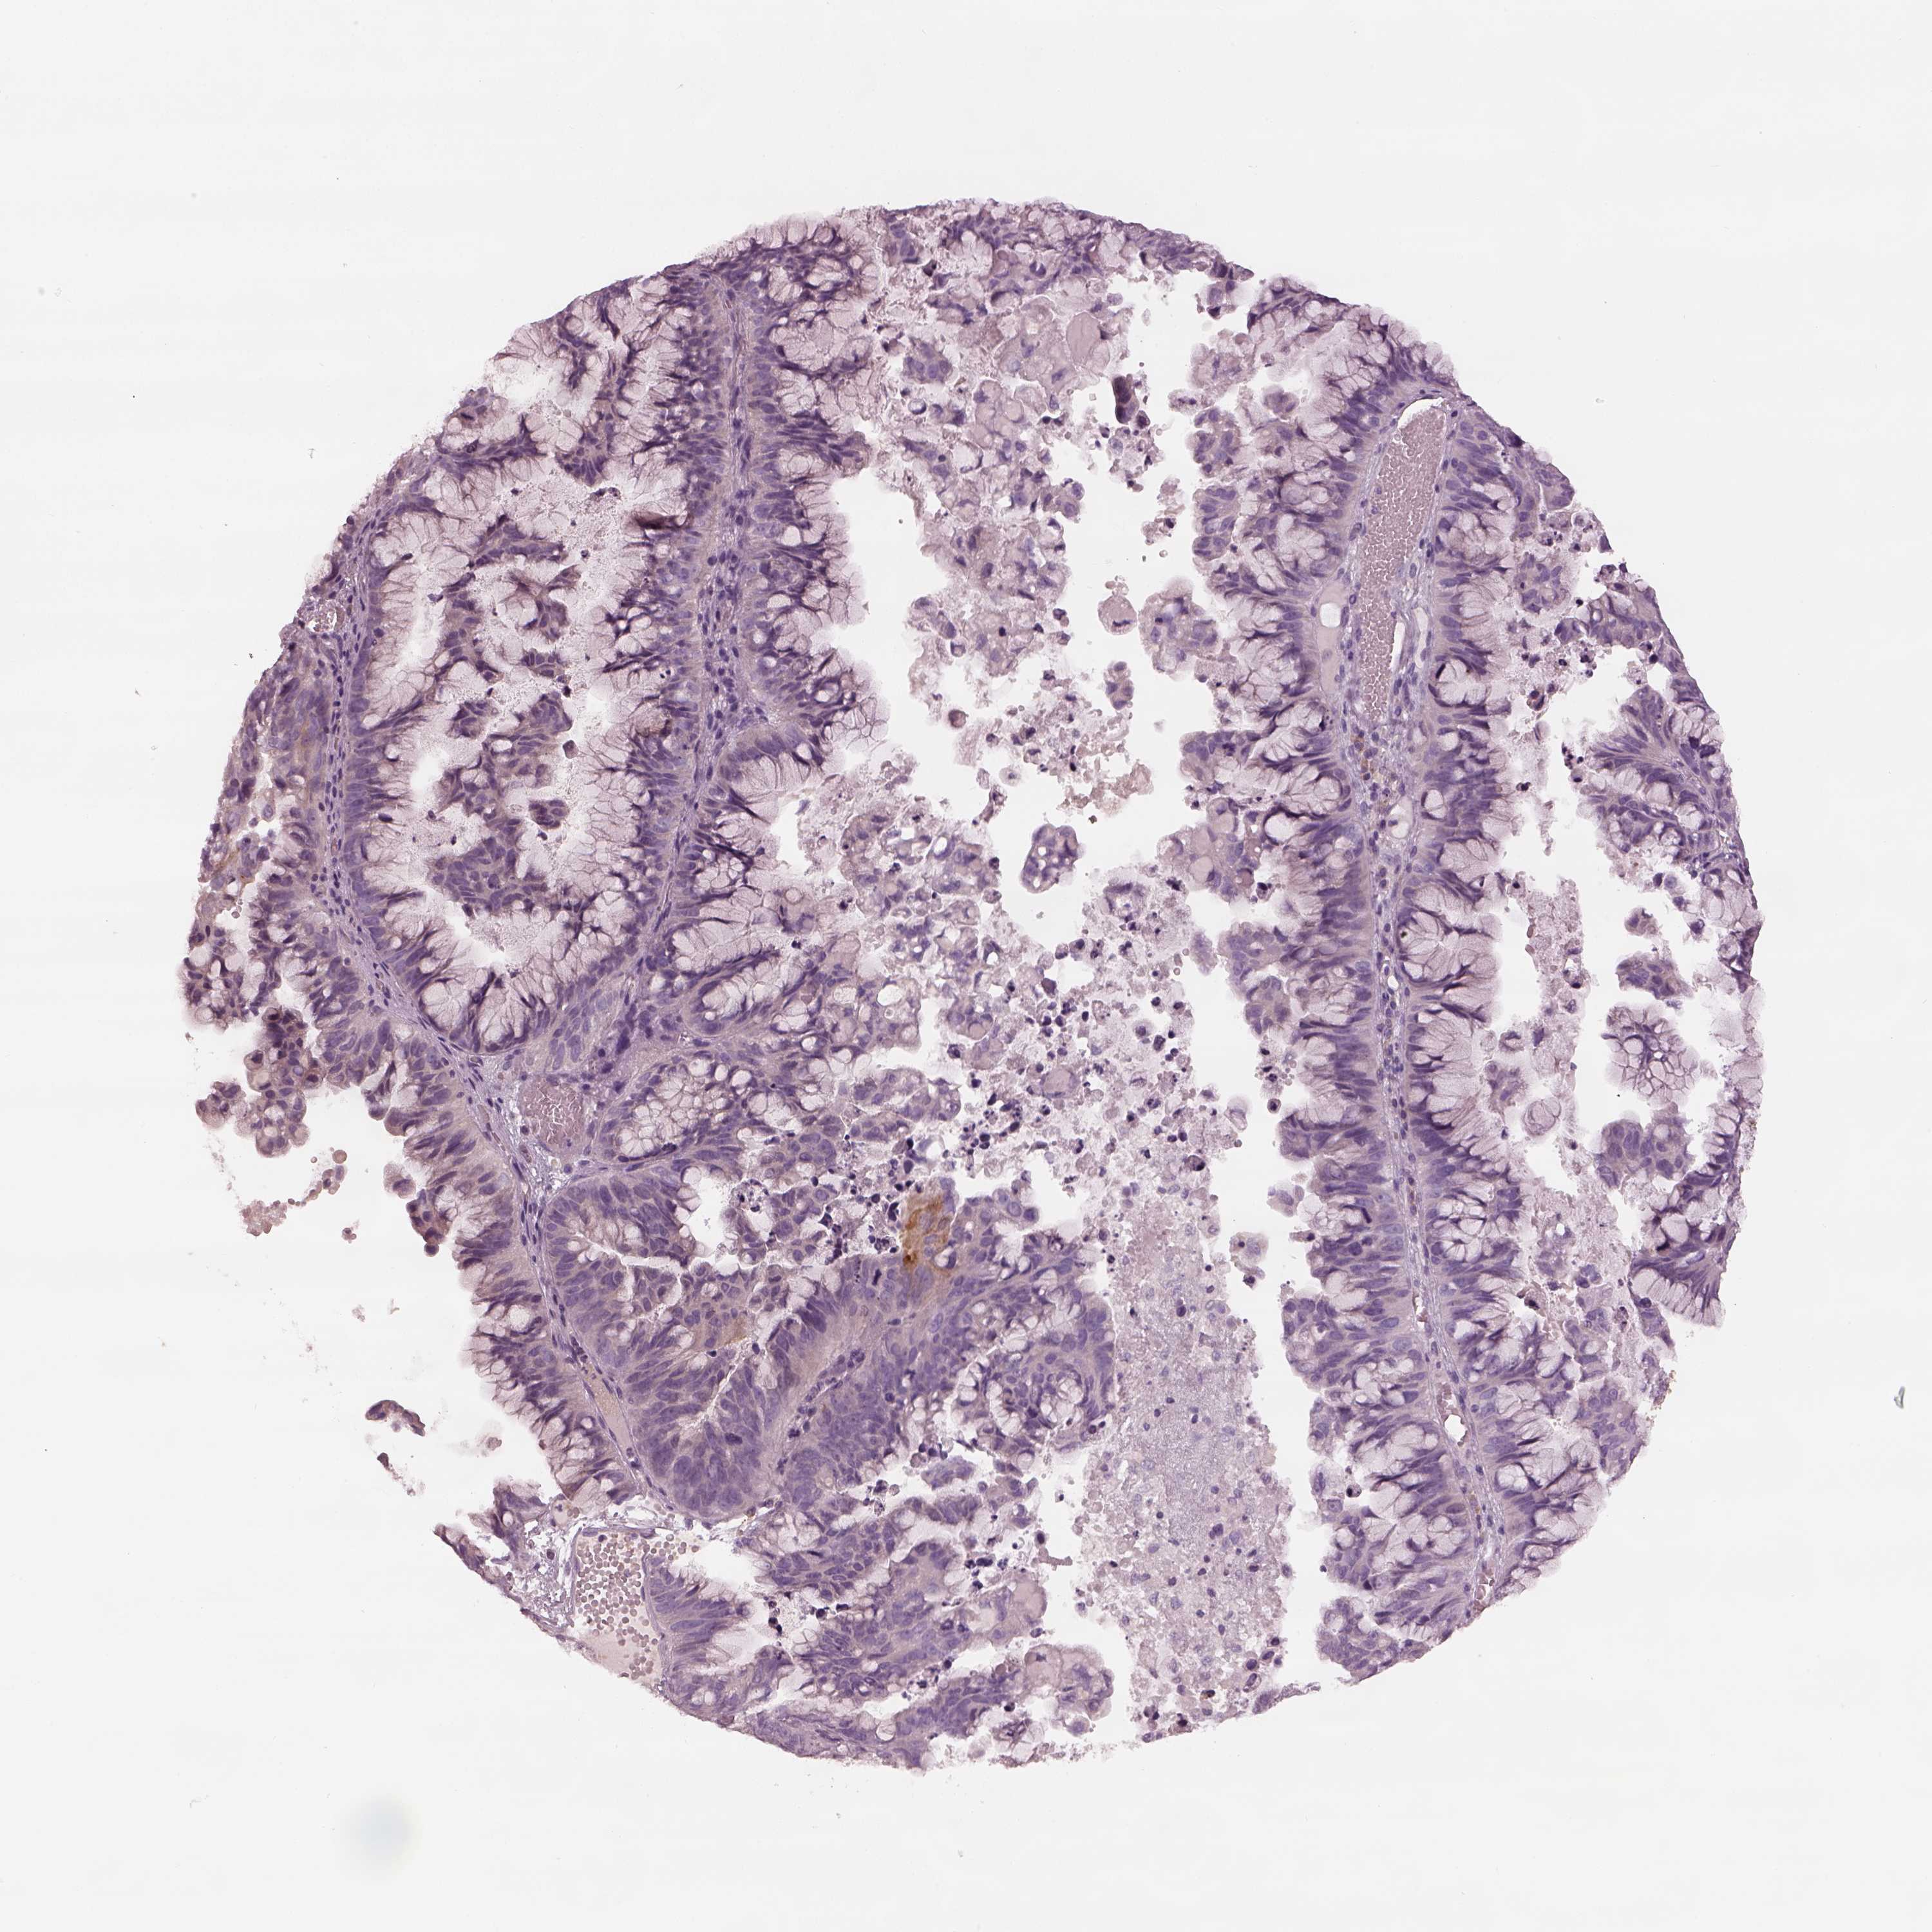

OVARIAN CANCER - Protein expressioni

A mouse-over function shows sample information and annotation data. Click on an image to view it in a full screen mode. Samples can be filtered based on level of antibody staining by selecting one or several of the following categories: high, medium, low and not detected. The assay and annotation is described here.

Note that samples used for immunohistochemistry by the Human Protein Atlas do not correspond to samples in the TCGA dataset.

Antibody stainingi

Antibody staining in the annotated cell types in the current human tissue is reported as not detected, low, medium, or high, based on conventional immunohistochemistry profiling in selected tissues. This score is based on the combination of the staining intensity and fraction of stained cells.

Each image is clickable and will lead to virtual microscopy that enables deeper exploration of all samples and also displays staining intensity scores, fraction scores and subcellular localization as well as patient and tissue information for each sample.

Antibody HPA042369

Cystadenocarcinoma, serous, NOS

Cystadenocarcinoma, mucinous, NOS

Carcinoma, endometroid